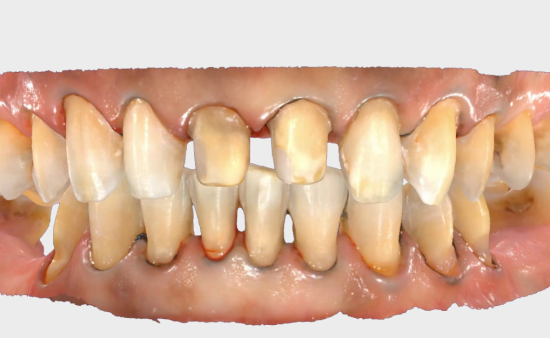

ステップ1: データ収集

セラミックベニアの場合、低侵襲アプローチで最小限の歯構造の縮小を使用することをお勧めします。

デジタルガイド付きベニヤ準備ワークフローは、CADソフトウェアを使用して最終的なベニヤに必要な最小厚さを計算することにより、正確な歯の減少を保証します。

修復後、有益な口腔内機能が観察されました。